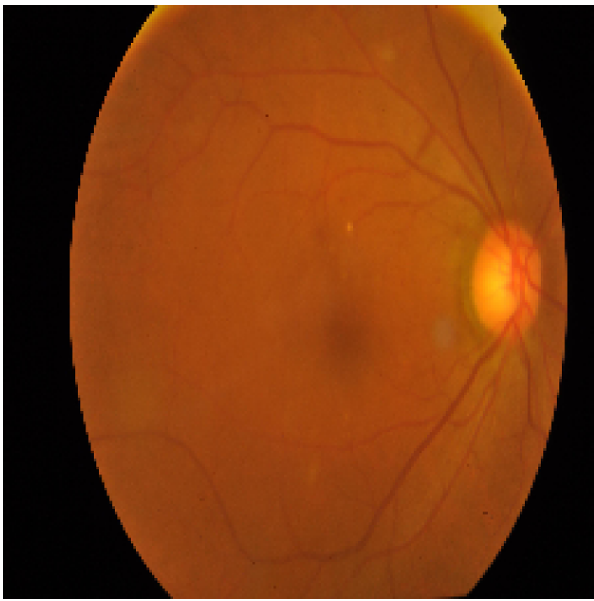

Figure 1: Illustration of the preprocessing pipeline applied to a fundus image. From left to right: (a) Original color image, (b) grayscale conversion used for HOG computation, and (c) corresponding Histogram of Oriented Gradients (HOG) visualization highlighting edge and texture features.